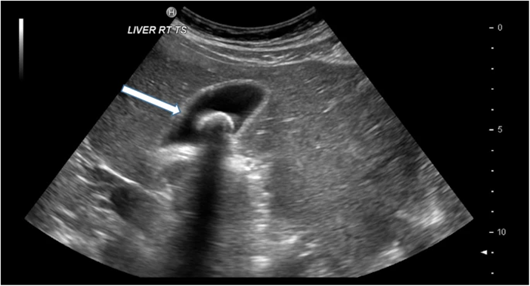

Ultrasound is the first-line imaging modality for the evaluation of suspected gallstones and biliary pathology. It is a useful imaging procedure for the detection of gallstones and evaluation of its mobility. On ultrasound, gallstones are characteristically echogenic and demonstrate posterior acoustic shadowing as seen in Figure 1 (Murphy et al., 2020). The ultrasound procedure also enables dynamic examination of gallstones where mobile stones will collect in the gallbladder’s dependent portion while impacted stones remain static (Evanson et al., 2025).

Figure 1: Ultrasound image of the gallbladder with a gallstone, demonstrating the typical appearance of echogenic structure with posterior acoustic shadowing (arrow) (Murphy et al., 2020)